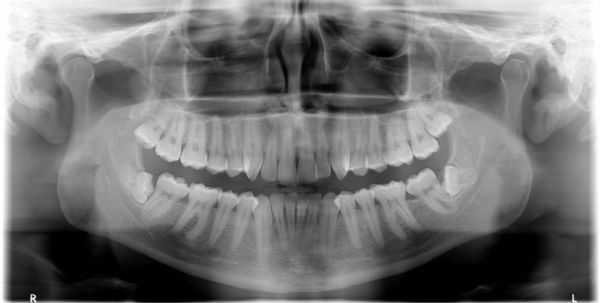

При первичном визуальном осмотре специалист определяет характер травмы без труда, так как признаки вывиха проявляются достаточно ярко. Но для более детального изучения характера и формы патологии (для оценки состояния челюсти, соседних зубов и иннервации в области повреждённого зуба) стоматолог назначает рентгенологическое исследование: ортопантомографию (ОПТГ) или компьютерную томографию челюсти . Это поможет дифференцировать вывих от иных форм травмы зуба (ушиба и перелома), кроме этого оценить структуру костной ткани, окружающей зуб на предмет трещин и перелома.